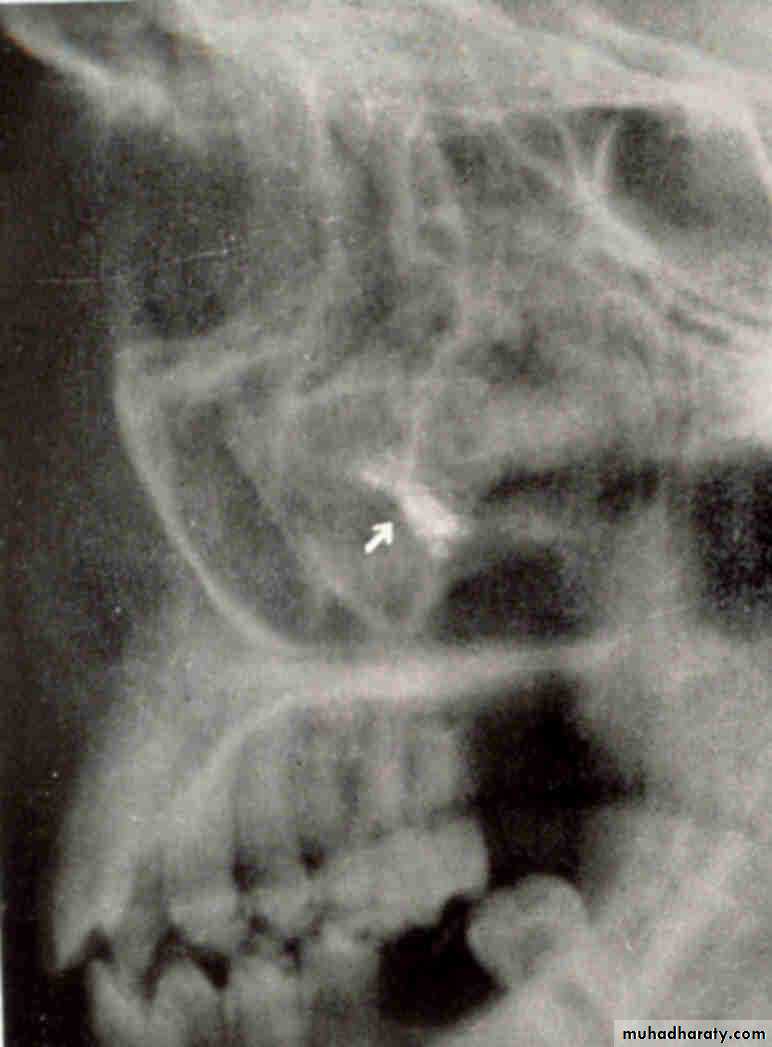

LATERAL VIEWLateral oblique

film placement for canine film

film placement for premolar filmPID placement for premolar film

PID placement for canine film

root tip

Lingual. The tube head moves mesially from the premolar film to the canine film. The object also moves mesially, starting out distal to the first molar on the premolar film and ending up mesial to the first molar on the canine film. This object represents the tip of the palatal root of the second molar and is located distal to the first molar and in a lingual relationship